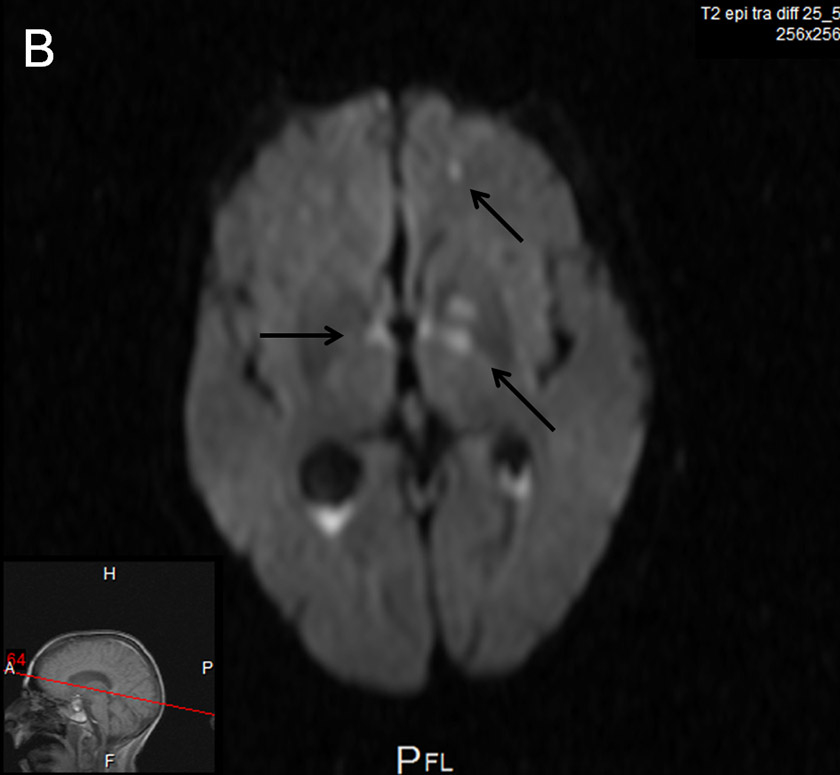

Cerebral MRI.

A, B Axial diffusion-weighted images: Areas of ischaemic necrosis in the pons (A), and thalami and basal ganglia bilaterally (B).

Two days later the patient became drowsy again with signs of upper brainstem dysfunction. Cerebral MRI showed meningeal enhancement and widespread punctate ischaemic-type lesions affecting vascular beds of both carotid and vertebral arteries bilaterally (fig. 1 A–C). MR angiography showed numerous irregularities of the distal arteries, suggestive of vasculitis (fig. 1D). Antibiotic treatment was broadened to include meropenem 3 × 2 g and dexamethasone was restarted but brainstem dysfunction did not improve. Supportive treatment was withdrawn and the patient died on day 21 post-surgery. Subsequent CSF cultures were sterile.